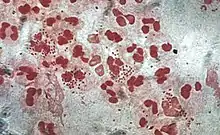

Monocytes develop in the bone marrow and reach maturity in the blood. Mature monocytes have large, smooth, lobed nuclei and abundant cytoplasm that contains granules. Monocytes ingest foreign or dangerous substances and present antigens to other cells of the immune system. Monocytes form two groups: a circulating group and a marginal group that remain in other tissues (approximately 70% are in the marginal group). Most monocytes leave the blood stream after 20–40 hours to travel to tissues and organs and in doing so transform into macrophages[70] or dendritic cells depending on the signals they receive.[71] There are about 500 million monocytes in one litre of human blood.[5]

Mature macrophages do not travel far but stand guard over those areas of the body that are exposed to the outside world. There they act as garbage collectors, antigen presenting cells, or ferocious killers, depending on the signals they receive.[72] They derive from monocytes, granulocyte stem cells, or the cell division of pre-existing macrophages.[73] Human macrophages are about 21 micrometers in diameter.[74]

This type of phagocyte does not have granules but contains many lysosomes. Macrophages are found throughout the body in almost all tissues and organs (e.g., microglial cells in the brain and alveolar macrophages in the lungs), where they silently lie in wait. A macrophage's location can determine its size and appearance. Macrophages cause inflammation through the production of interleukin-1, interleukin-6, and TNF-alpha.[75] Macrophages are usually only found in tissue and are rarely seen in blood circulation. The life-span of tissue macrophages has been estimated to range from four to fifteen days.[76]